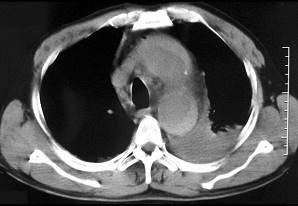

问题 男,58岁,有高血压病史,突发胸背剧痛,CT扫描如图,其最可能的诊断为 ( )

选项 A.主动脉瘤 B.主动脉假性动脉瘤 C.主动脉窦瘤破裂 D.高安氏病 E.主动脉夹层动脉瘤

答案 E